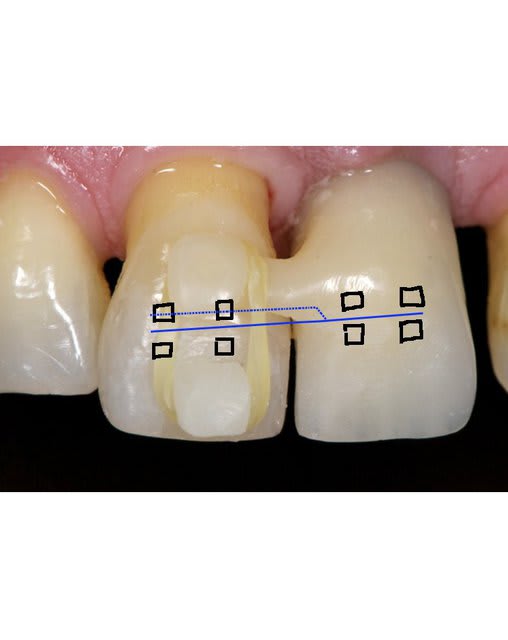

Le probllème que tu a en ortho habituellement c'est la force de reaction, donc quand tu veux bouger une dents pour limiter ces effets tu es obliger de prendre appuis sur plusieurs dents.

La tu utilise un implant donc pas besoin de se soucier de la force de réaction. L'implant il ne va pas bouger. Donc un système avec deux brackets et parfaitement gérable au niveau mécanique.

Pour ingresser la dent tu fait juste un pliage du type sur le dessins.

SI la dent procline tu plie le fil en lingual.

Par contre attention vue qu'il s''agit d'un intrusion sur un terrain paro je dirais qu'il ne faut utiliser que des fils de faible diamètre car il ne doivent surtout pas remplir le slot.

Ici il y aurait une très bonne indication pour des danchemon.

Normalement tu dois tout pouvoir faire avec un Niti 0.014.

Ps : sur le shema j'ai mis les bracket en vestibulaire mais il n'y a strictement aucun problème pour les mettre en lingual, mis a part que le pliage devient beaucoup plus délicat.